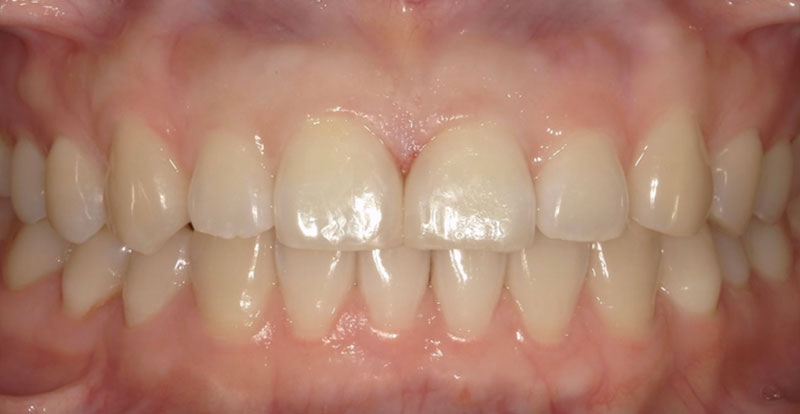

患者様は「右上2番目の歯が内側に入っていること」および「前歯の突出感(クチゴボ)」を主訴として来院されました。

本来であれば抜歯を含めた全顎矯正が望ましいケースでしたが、患者様のご希望により短期間での部分矯正を行いました。

部分矯正では上下顎前突の大きな改善は難しい旨を事前にご説明し、ご了承のうえ治療を開始しました。

治療の結果、交叉咬合(シザーズバイト)となっていた上下前歯部は、正常被蓋(上の歯が下の歯を適切に覆う状態)を獲得することができ、歯列の整った状態に仕上がりました。

患者様には「きれいに並んだ歯」をご覧いただき、大変ご満足いただけています。

| 主訴 | 右上2番目の歯の内側転位 |

| 所見 | 左右2番交叉咬合、上下顎前突 |

| 治療装置 | マルチブラケット |

| 装置装着部位 | 上下3〜3の12本 |

| 治療費 | 33万円(税込) |

| 治療期間 | 約6か月(約10回通院) |